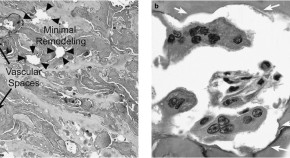

The authors examined late- and early-onset murine retinoblastoma tumors and noted that aggressive tumors uniquely expressed an immune gene expression signature. This led to accumulation of a variety of immune cells, including T-lymphocytes, that was not observed in less aggressive tumors. Gene expression analysis identified the immune signature in human and other murine tumors, and they observed it correlated with less proliferative tumors.